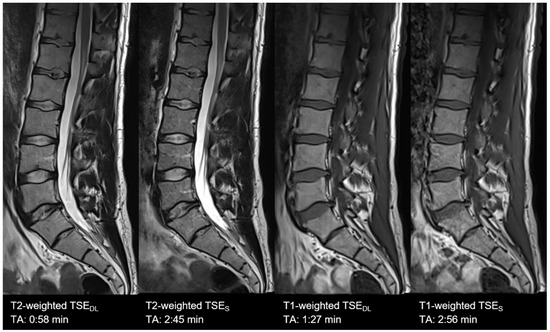

| Lumbar spine | TSES | T1 TSE | sagittal | 2:56 | 300 | 0.9 × 0.9 × 3.0 | 1 | 2 | 0 | 562 | 10 | 150 | 180 | 10.4 |

| T2 TSE FS | sagittal | 2:45 | 300 | 0.7 × 0.7 × 3.0 | 2 | 1 | 2 | 6040 | 102 | 150 | 189 | 11.3 | ||

| TSEDL | T1 TSE | sagittal | 1:27 | 300 | 0.9 × 0.9 × 3.0 | 1 | 2 | 3 | 462 | 10 | 150 | 180 | 10.4 | |

| T2 TSE FS | sagittal | 0:58 | 300 | 0.7 × 0.7 × 3.0 | 1 | 1 | 3 | 4470 | 105 | 150 | 189 | 10.5 | ||